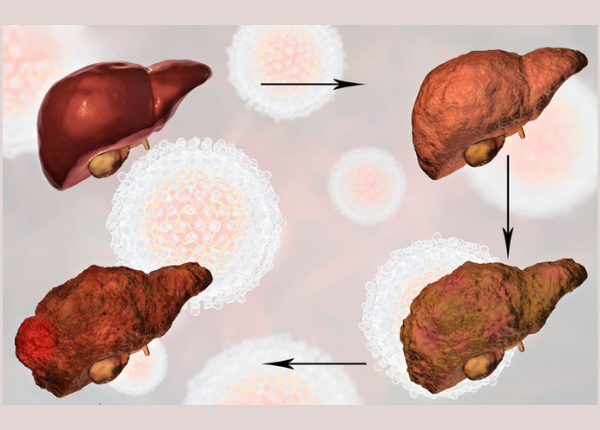

Viêm gan mạn tính là gì? Bệnh này có nguy hiểm không?

Viêm gan mạn tính là tình trạng viêm kéo dài ở mô gan, gây tổn thương tế bào gan một cách âm thầm nhưng liên tục. Nếu không được phát hiện và kiểm soát kịp thời, bệnh có thể tiến triển thành xơ gan, suy gan hoặc ung thư gan. Tổn thương gan là gì? ...

Xơ gan là bệnh gì? Có nguy hiểm không?

Xơ gan là một bệnh lý mạn tính, trong đó nhu mô gan bị tổn thương và thay thế bởi mô xơ, gây rối loạn cấu trúc và suy giảm nghiêm trọng chức năng gan. Quá trình này diễn ra âm thầm nhưng kéo dài, khiến gan mất dần khả năng giải độc, tổng hợp ...

Xơ gan do rượu có chữa khỏi hoàn toàn được không?

Xơ gan làm suy giảm chức năng gan, khi đó gan không còn thực hiện tốt các nhiệm vụ như lọc và thải độc, chuyển hóa chất dinh dưỡng, tổng hợp protein và sản xuất các yếu tố đông máu. Nếu không được phát hiện và điều trị sớm, xơ gan nhất là xơ gan ...